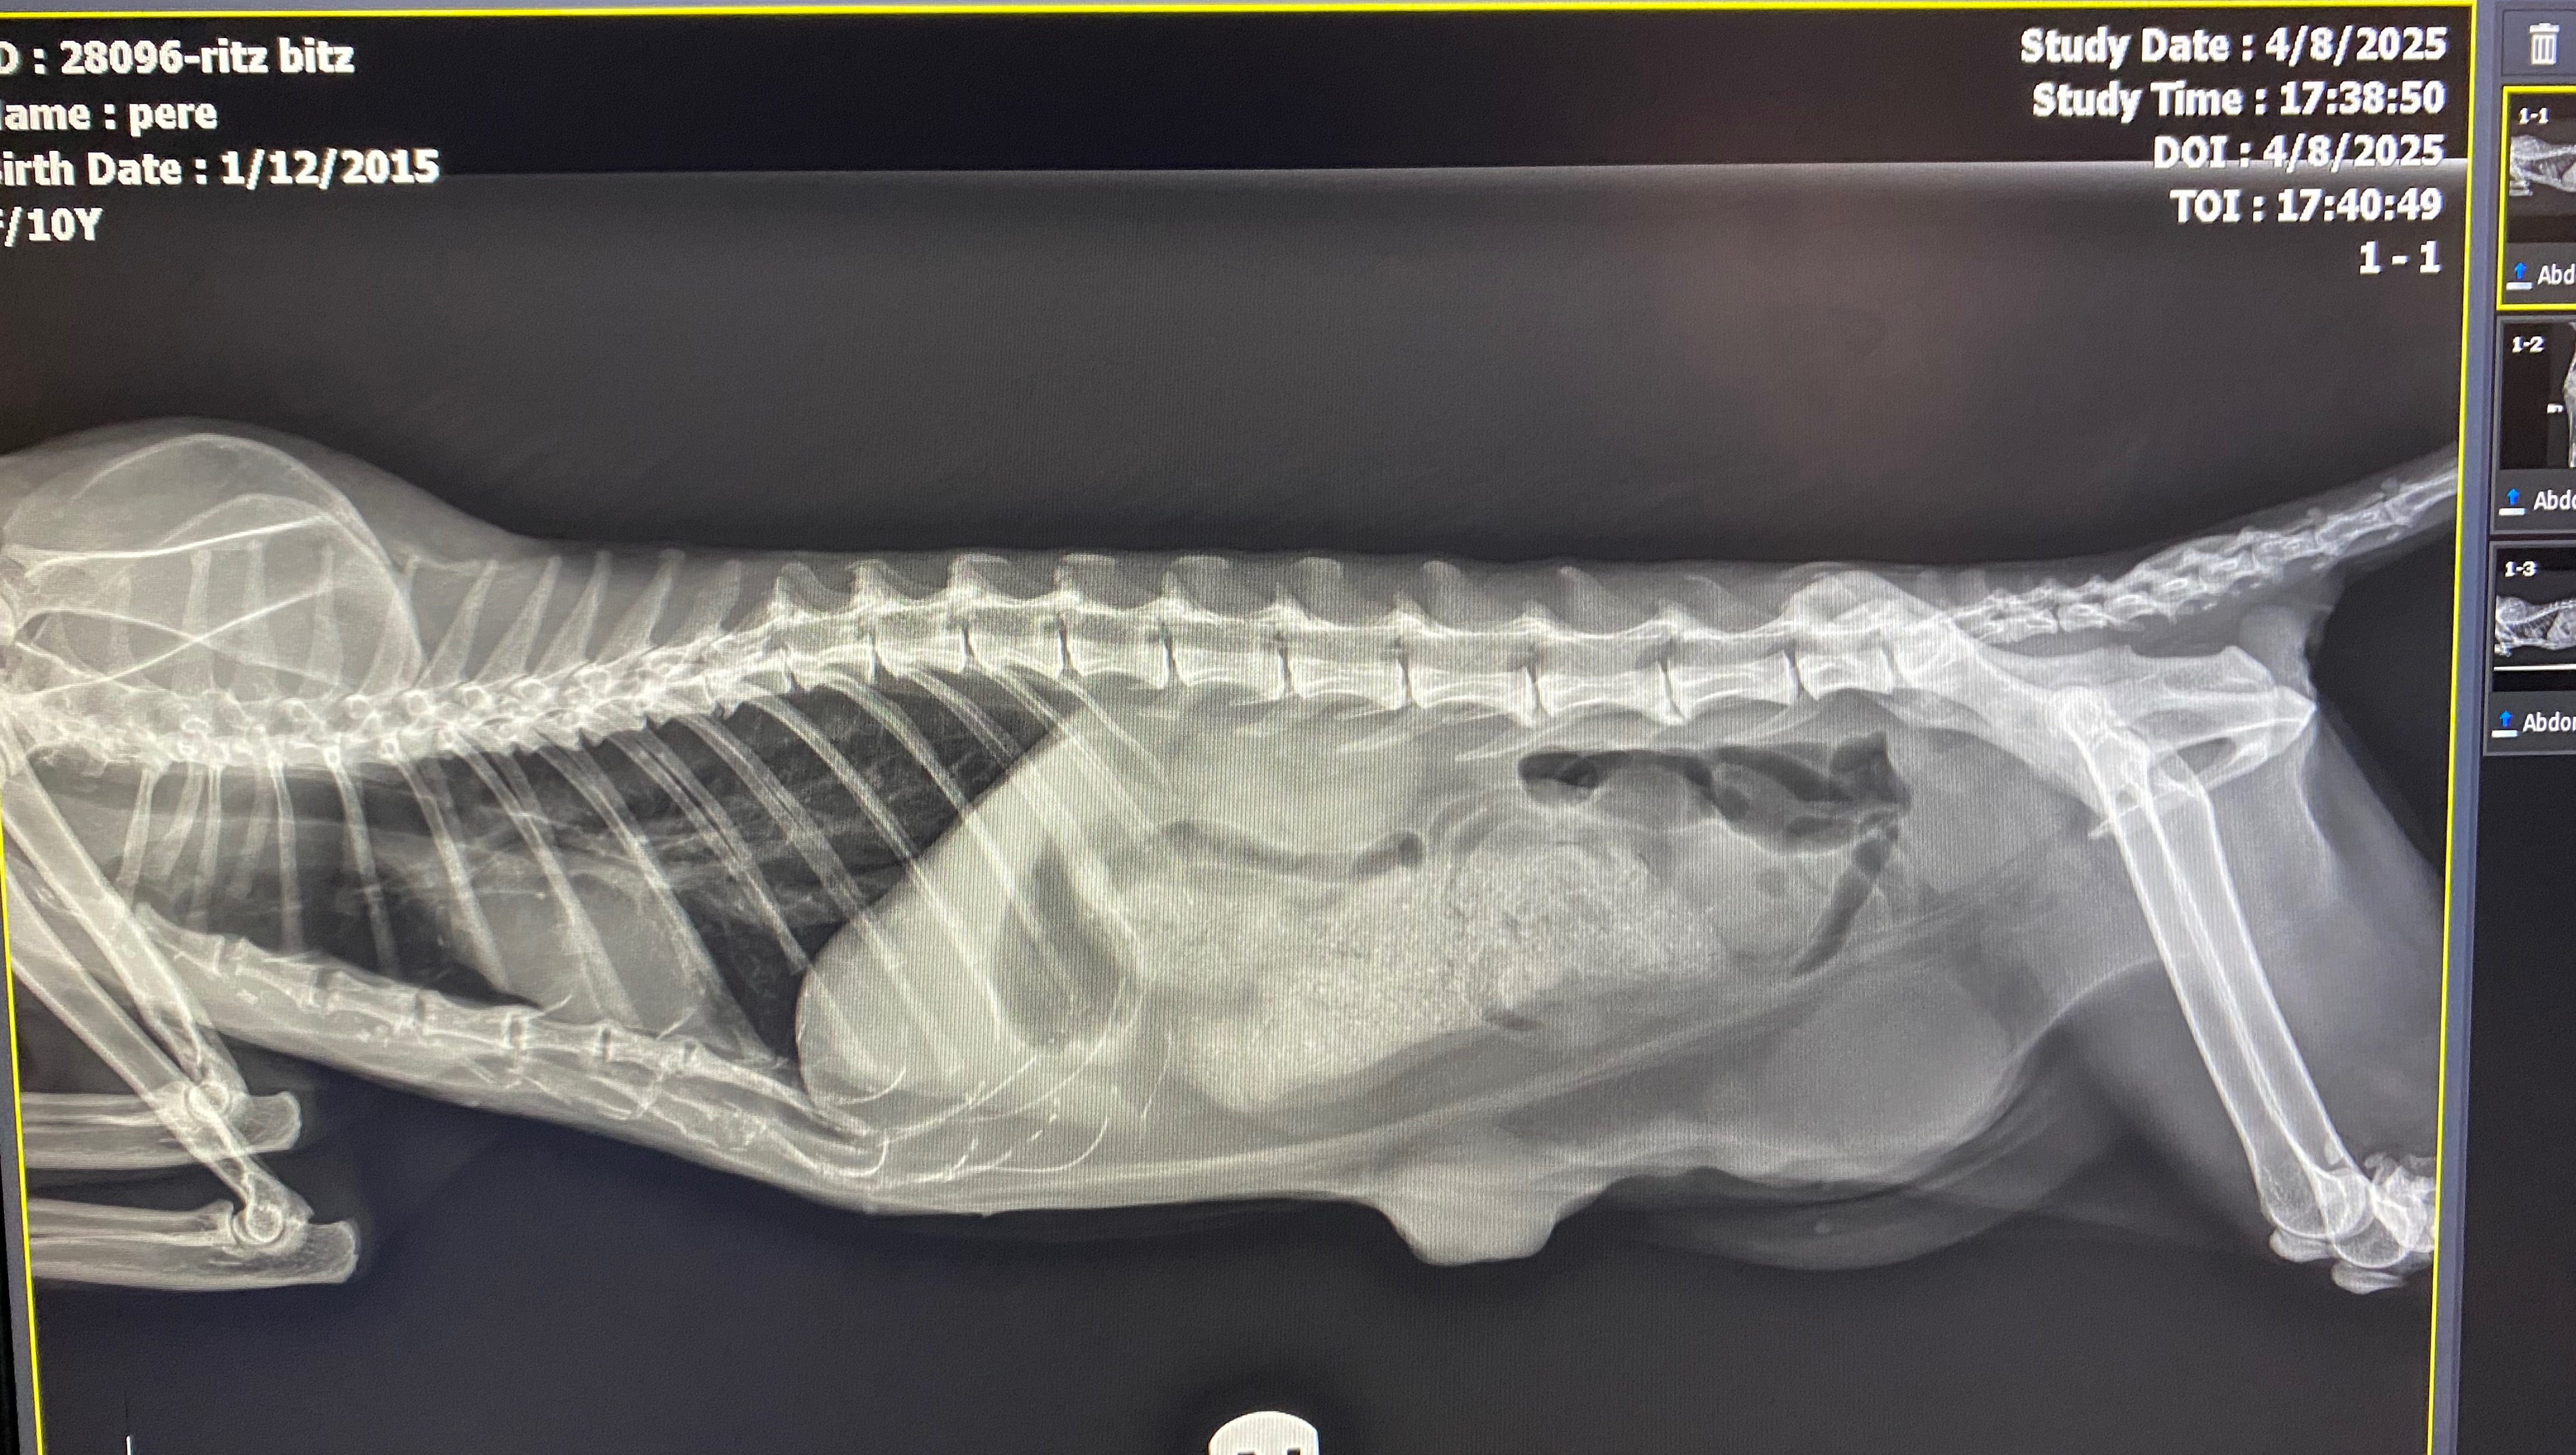

Donation protected